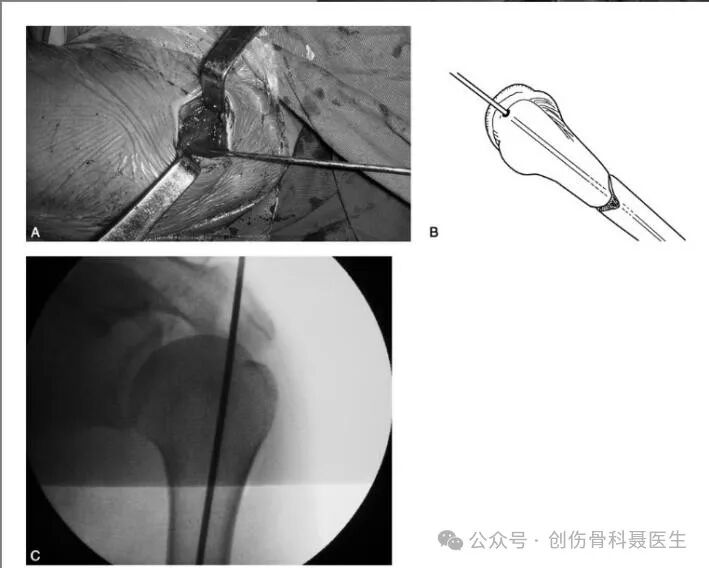

❷梨状窝进针点:大转子内侧的凹陷(股骨颈底部凹陷处)的闭孔外肌附着区

④股骨干逆行交锁髓内钉技术:

切口入点:屈膝30°,理想进入点为后交叉韧带股骨起点前1.2cm(与髓腔一致)和髁间窝中央.